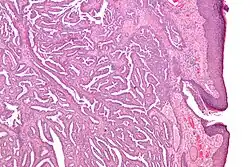

| Micrograph of a nipple adenoma. H&E stain. | |

Once excised, the macroscopic appearance of nipple adenomas is of a poorly defined nodular mass. The microscopic appearance can be quite bizarre, and may be misinterpreted as a carcinoma. Nipple adenomas usually have a rounded outline at low magnification, and at higher magnification can be seen to consist of a haphazardly arranged mass of proliferating tubular structures composed of epithelial and myoepithelial cells within varying amounts of fibrous stroma. The epithelial cells are usually columnar, but the columnar epithelial cells can undergo apocrine or squamous metaplasia. Mitotic figures and necrosis are not commonly seen.[1]